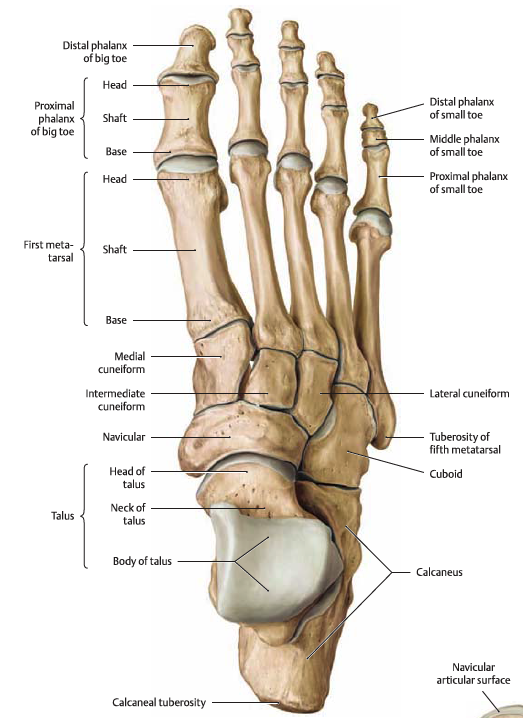

경골 - 거골 - 종골 - 주상골과 입방골, 설상골 - 중족골

- 까치발로 서면 경골 - 거골 - 주상골 - cuneiform bone - metatsal bone